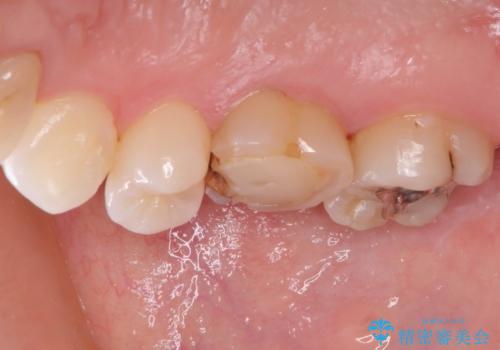

他院で矯正治療をされていたそうですが、矯正治療前から変色は気になっており、歯並びが整ってからは、より気になるようになっていたそうです。

自然に仕上がり、患者様には大変満足していただきました。